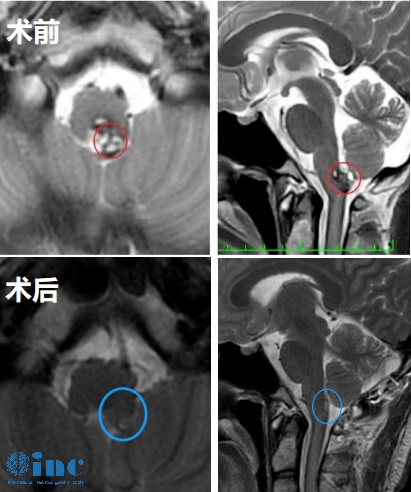

50岁女性-延髓海绵状血管瘤

28岁女性-脑干延髓海绵状血管瘤

19岁男孩-延髓海绵状血管瘤

32岁男性-延髓海绵状血管瘤

30岁女性-延髓-颈髓海绵状血管瘤